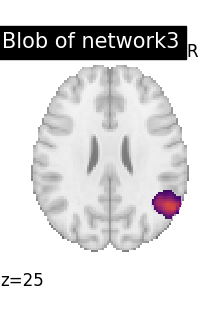

# To reduce the complexity, we choose to display all the regions

# extracted from network 3

import numpy as np

DMN_network = index_img(atlas_networks, 3)

regions_indices_network3 = np.where(np.array(extraction.index_) == 3)

for index in regions_indices_network3[0]:

cur_img = index_img(extraction.regions_img_, index)

coords = find_xyz_cut_coords(cur_img)

plotting.plot_stat_map(

cur_img,

display_mode="z",

cut_coords=coords[2:3],

title="Blob of network3",

colorbar=False,

cmap="inferno",

vmax=15,

)